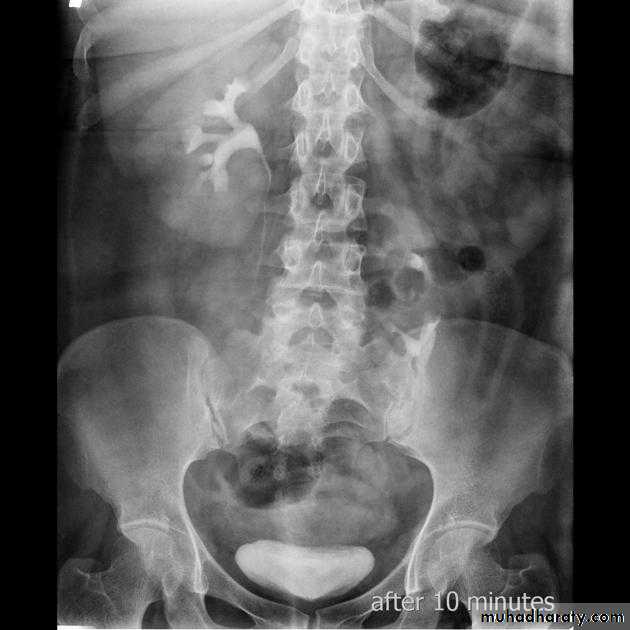

( PUJ OBSTRUCTION ):IVU shows :

Marked dilatation of pelvis and may be extra-renal.

Calyceal dilatation is late and in advanced cases form foot shape PCS

The ureter is not seen and when it is seen looksnormal .

Delayed film with I.V. diuretic produce gross dilatation .